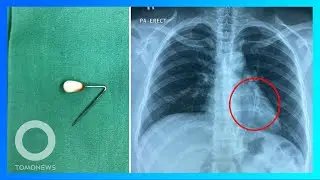

Jarum pentul tertelan saat wanita ini sedang merapikan hijab - TomoNews